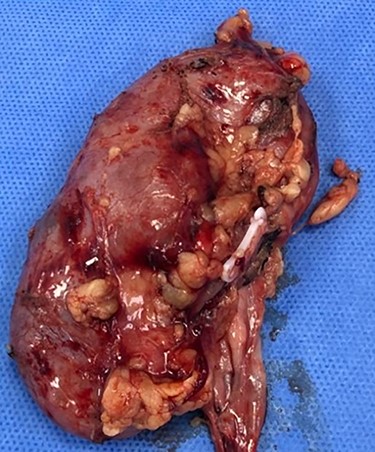

Consequently, the patient was scheduled for Rt radical nephrectomy which was done through Rt transverse paramedian incision. The renal specimen is shown in Fig. 5. The postoperative course went smoothly except for the wound infection which was managed conservatively. Histopathological examination showed that it was clear cell renal carcinoma, grade 2, T3a, free renal vein and lymph nodes were also free from any metastatic deposits (Score0/8; Fig. 6).